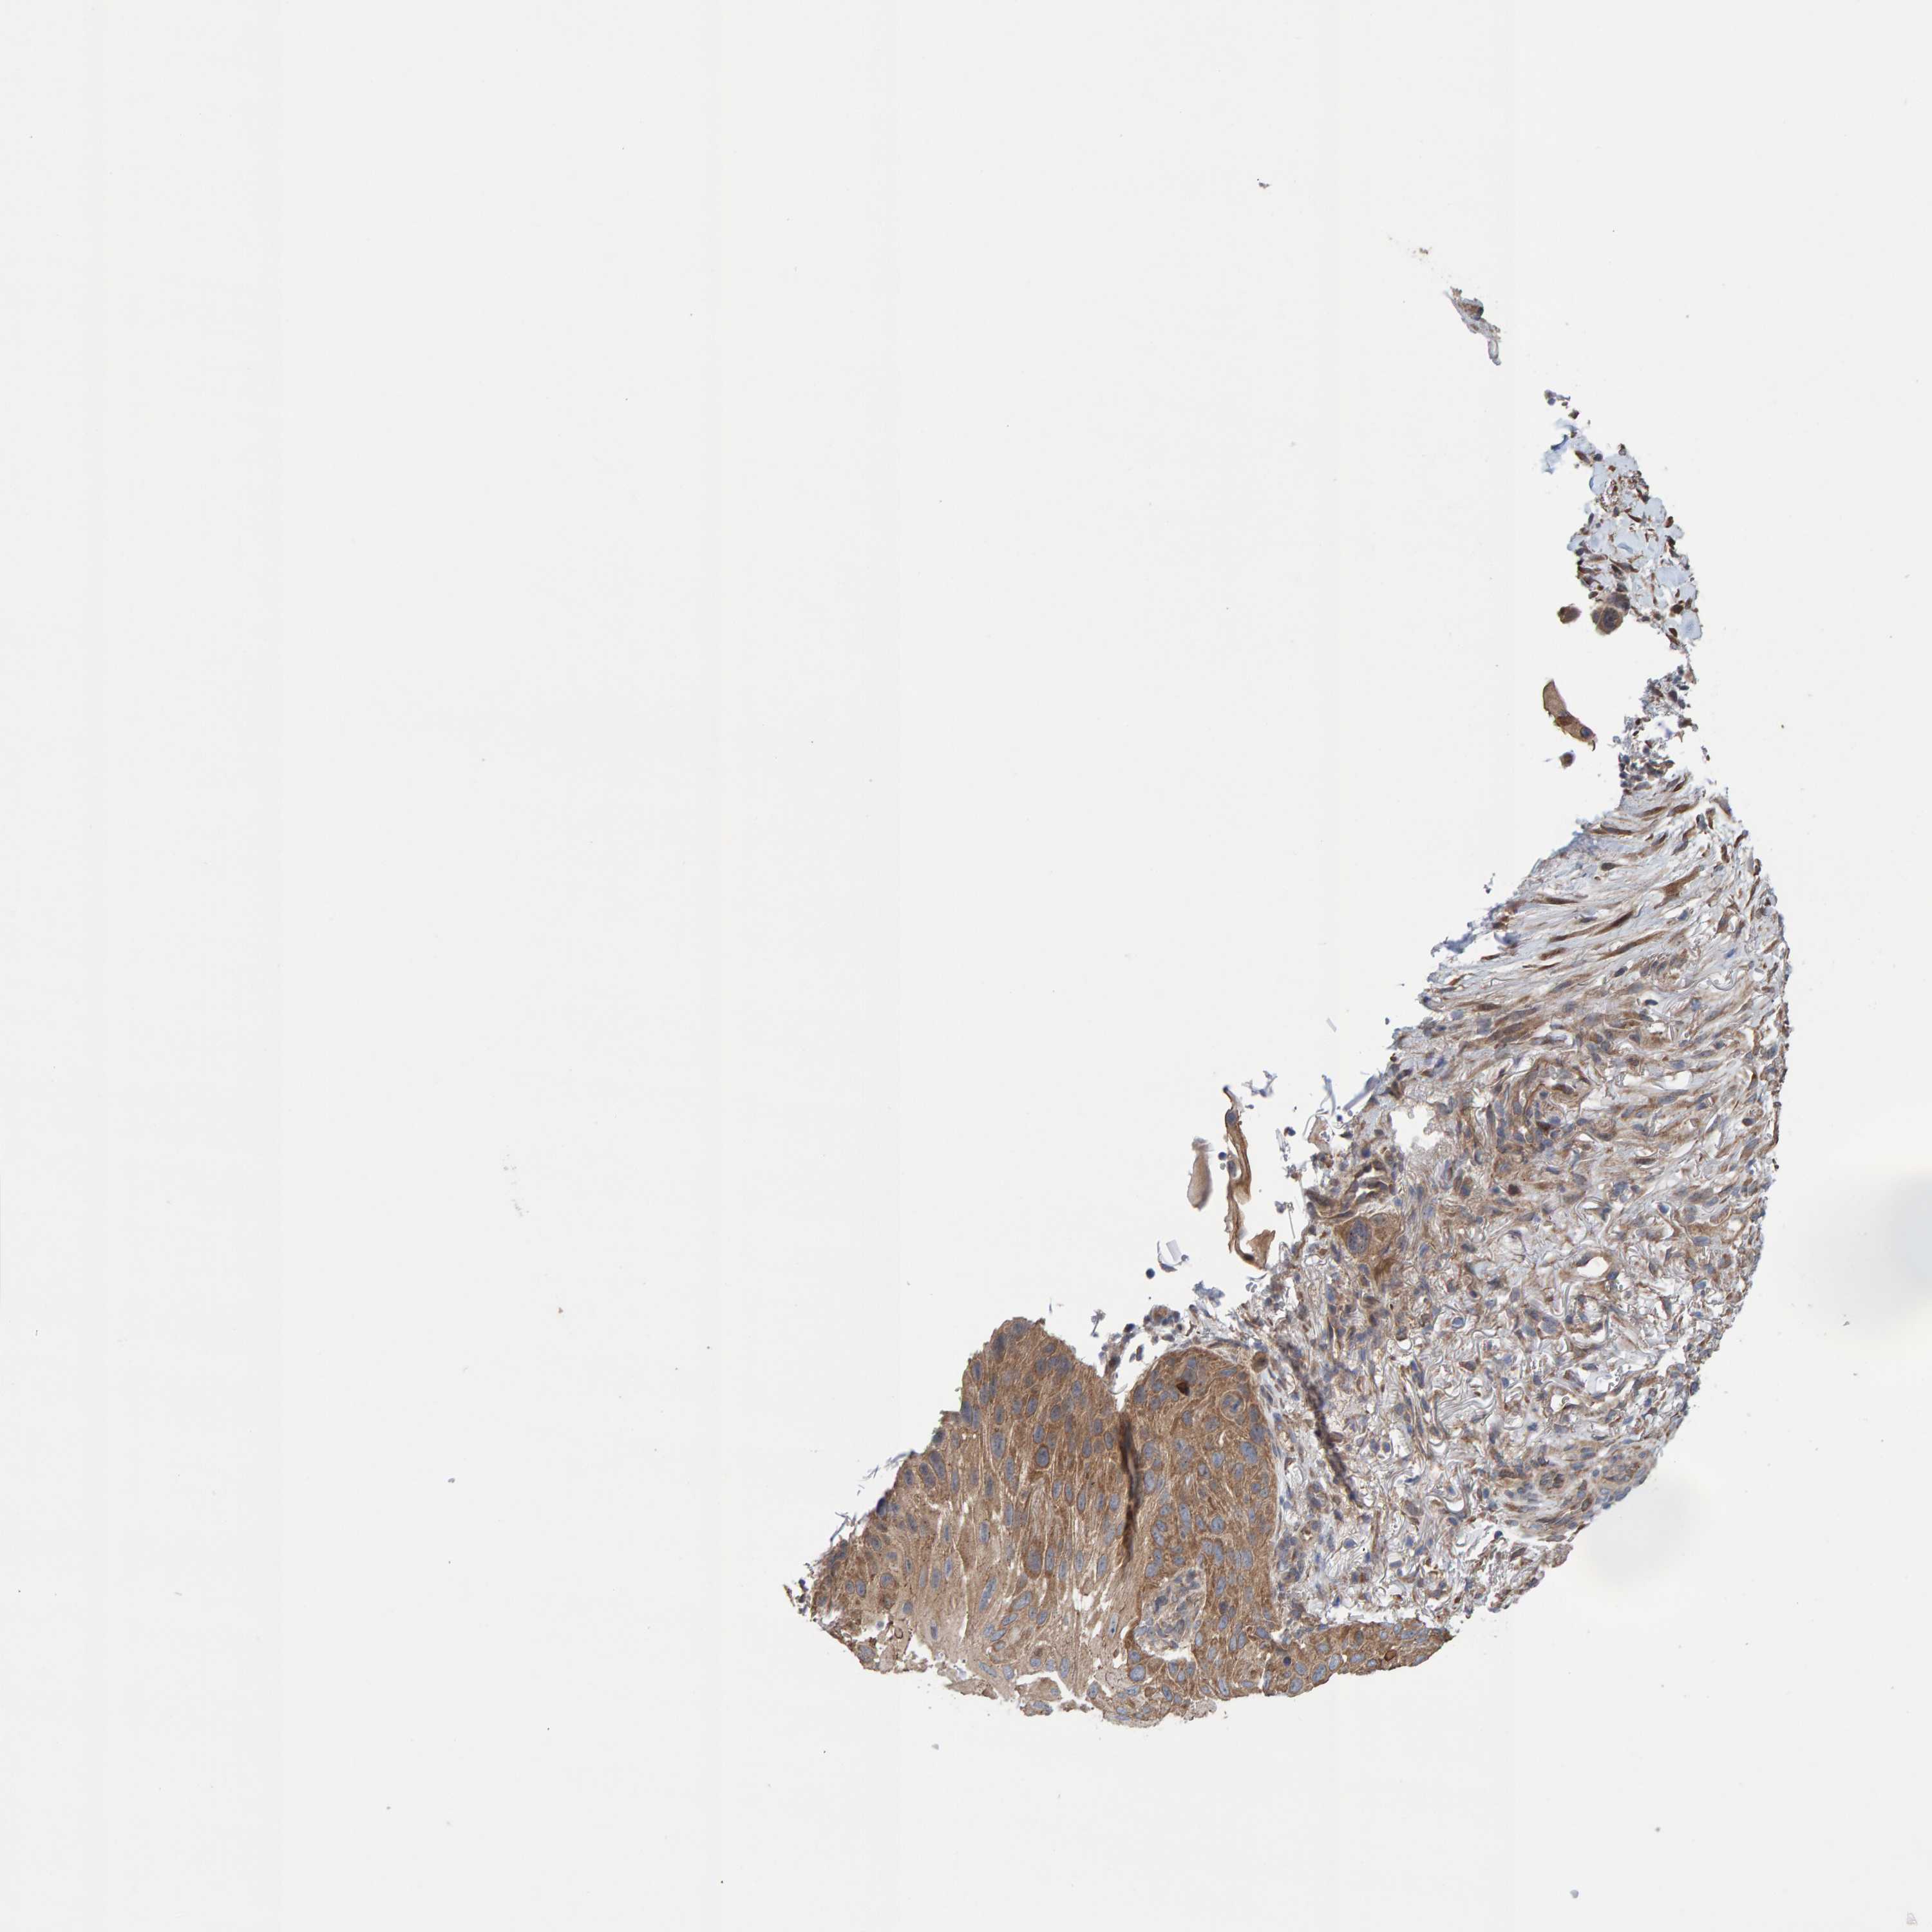

SKIN CANCER - Protein expressioni

A mouse-over function shows sample information and annotation data. Click on an image to view it in a full screen mode. Samples can be filtered based on level of antibody staining by selecting one or several of the following categories: high, medium, low and not detected. The assay and annotation is described here.

Antibody stainingi

Antibody staining in the annotated cell types in the current human tissue is reported as not detected, low, medium, or high, based on conventional immunohistochemistry profiling in selected tissues. This score is based on the combination of the staining intensity and fraction of stained cells.

Each image is clickable and will lead to virtual microscopy that enables deeper exploration of all samples and also displays staining intensity scores, fraction scores and subcellular localization as well as patient and tissue information for each sample.

Antibody HPA021403

Basal cell carcinoma